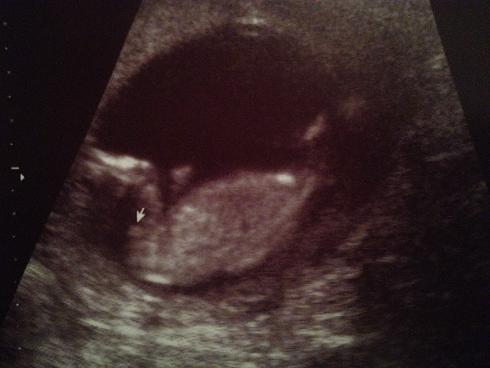

Attachment 11205 Attachment 11206 Attachment 11207

AAA I think girl!!!! Beautiful baby!!!!!!!

Looks like a little girl - congrats crystalclear!

Does look girly :)

Maybe pink.

I think girl x